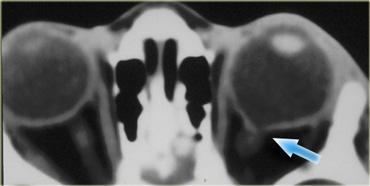

Bên trái là hình ảnh của một bệnh nhân bị giãn tĩnh mạch hốc mắt, người này nhận thấy mắt trái bị lồi ra khi rặn.

Hình trên là lúc nghỉ ngơi và hình dưới là trong nghiệm pháp Valsalva tại thời điểm hắt hơi.

Trong nghiệm pháp Valsalva, tĩnh mạch giãn giãn nở cực độ (mũi tên đỏ).

Lưu ý rằng trong nghiệm pháp Valsalva, tĩnh mạch mắt trên ở bên bình thường cũng giãn ra (mũi tên xanh).Kết luận